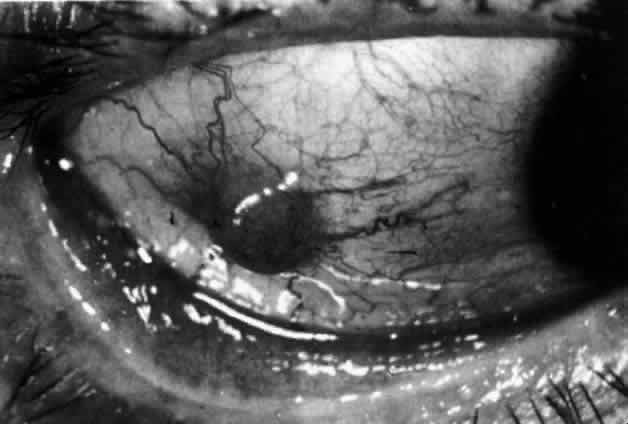

and adequate treatment can prevent these changes from becoming irreversible.  Fig. 27. In scleritis, maximum congestion occurs in deep episcleral plexus, which

is bowed forward by underlying scleral edema. Episcleral tissue is slightly

infiltrated and superficial plexus is slightly congested (see Fig. 14). (Watson PG, Hayreh S, Awdry P: Episcleritis and scleritis. Br J Ophthalmol 52:278–279, 1968) Fig. 27. In scleritis, maximum congestion occurs in deep episcleral plexus, which

is bowed forward by underlying scleral edema. Episcleral tissue is slightly

infiltrated and superficial plexus is slightly congested (see Fig. 14). (Watson PG, Hayreh S, Awdry P: Episcleritis and scleritis. Br J Ophthalmol 52:278–279, 1968)

|